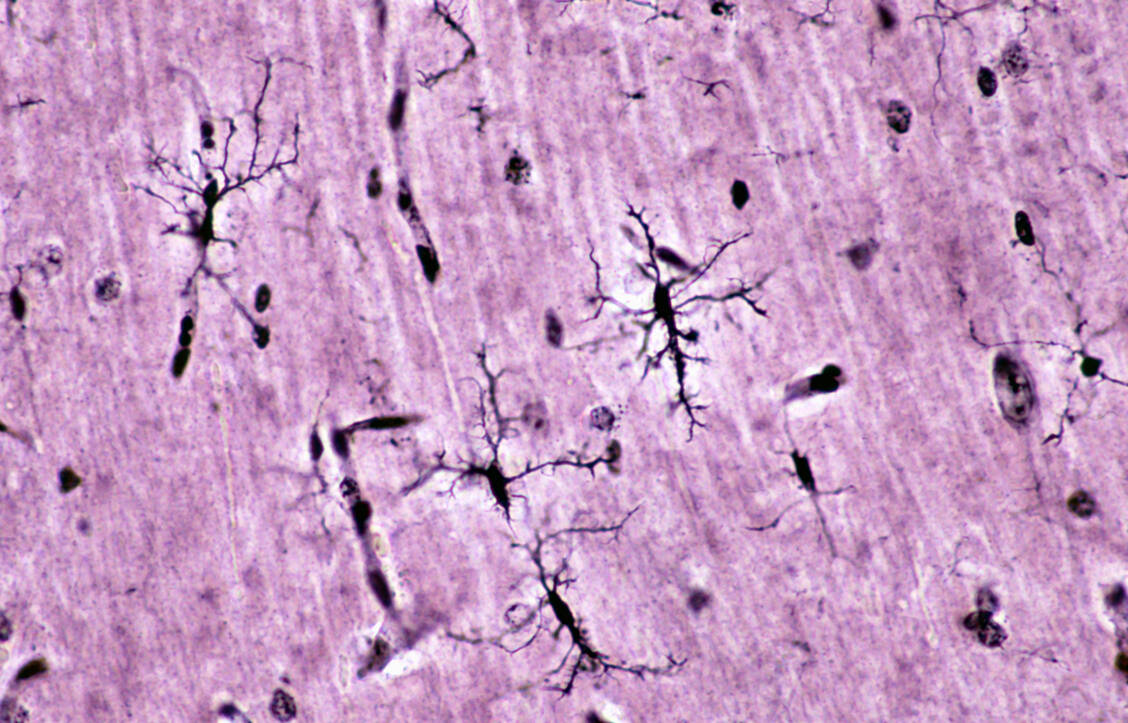

Mikrogliazellen gelten als Immunzellen des Gehirns. Sie spüren Krankheitserreger, Zellreste oder schädliche Ablagerungen auf und beseitigen diese. Um diesen Job optimal erledigen zu können, sind sie mit hochbeweglichen Fortsätzen ausgestattet, mit denen sie das Gehirn 24/7 abtasten. »Man kann sich Mikroglia wie einen Tintenfisch vorstellen, der mit seinen Tentakeln ständig seine Umgebung überprüft«, vergleicht Professor Dr. Christian Madry vom Institut für Neurophysiologie der Charité in Berlin in einer Pressemeldung der Alzheimer Forschung Initiative.

Madry und Kollegen haben aktuelle Forschungsergebnisse im Fachjournal »Science Advances« veröffentlicht. Sie konnten zeigen, dass das Protein CLIC1 (Chloride Intracellular Channel 1) in den Mikrogliazellen bei zwei Mechanismen von enormer Bedeutung ist. Einerseits steuert das Protein die Beweglichkeit der Mikroglia-Fortsätze. Im frühen Krankheitsstadium einer Alzheimer-Erkrankung können die Mikrogliazellen lösliches β-Amyloid (Aβ) schnell beseitigen, noch bevor schädliche Plaques entstehen. »Ohne CLIC1 verlieren die Zellen ihre typische Verästelung und ihre Fähigkeit, das Gewebe zu überwachen. Dadurch können sie schädliche Veränderungen, etwa alzheimertypische Aβ-Ablagerungen, weniger effektiv erkennen und beseitigen«, so Madry.